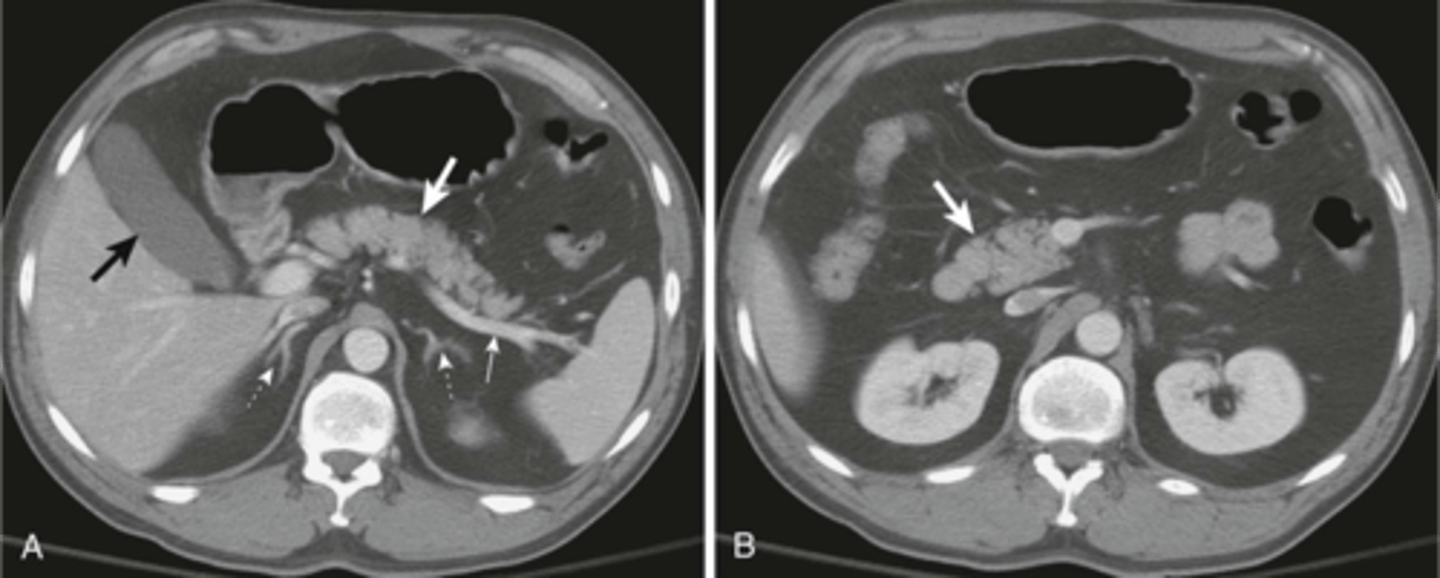

Normal anatomy in axial CT

Normal CT

Normal small and large bowel on CT